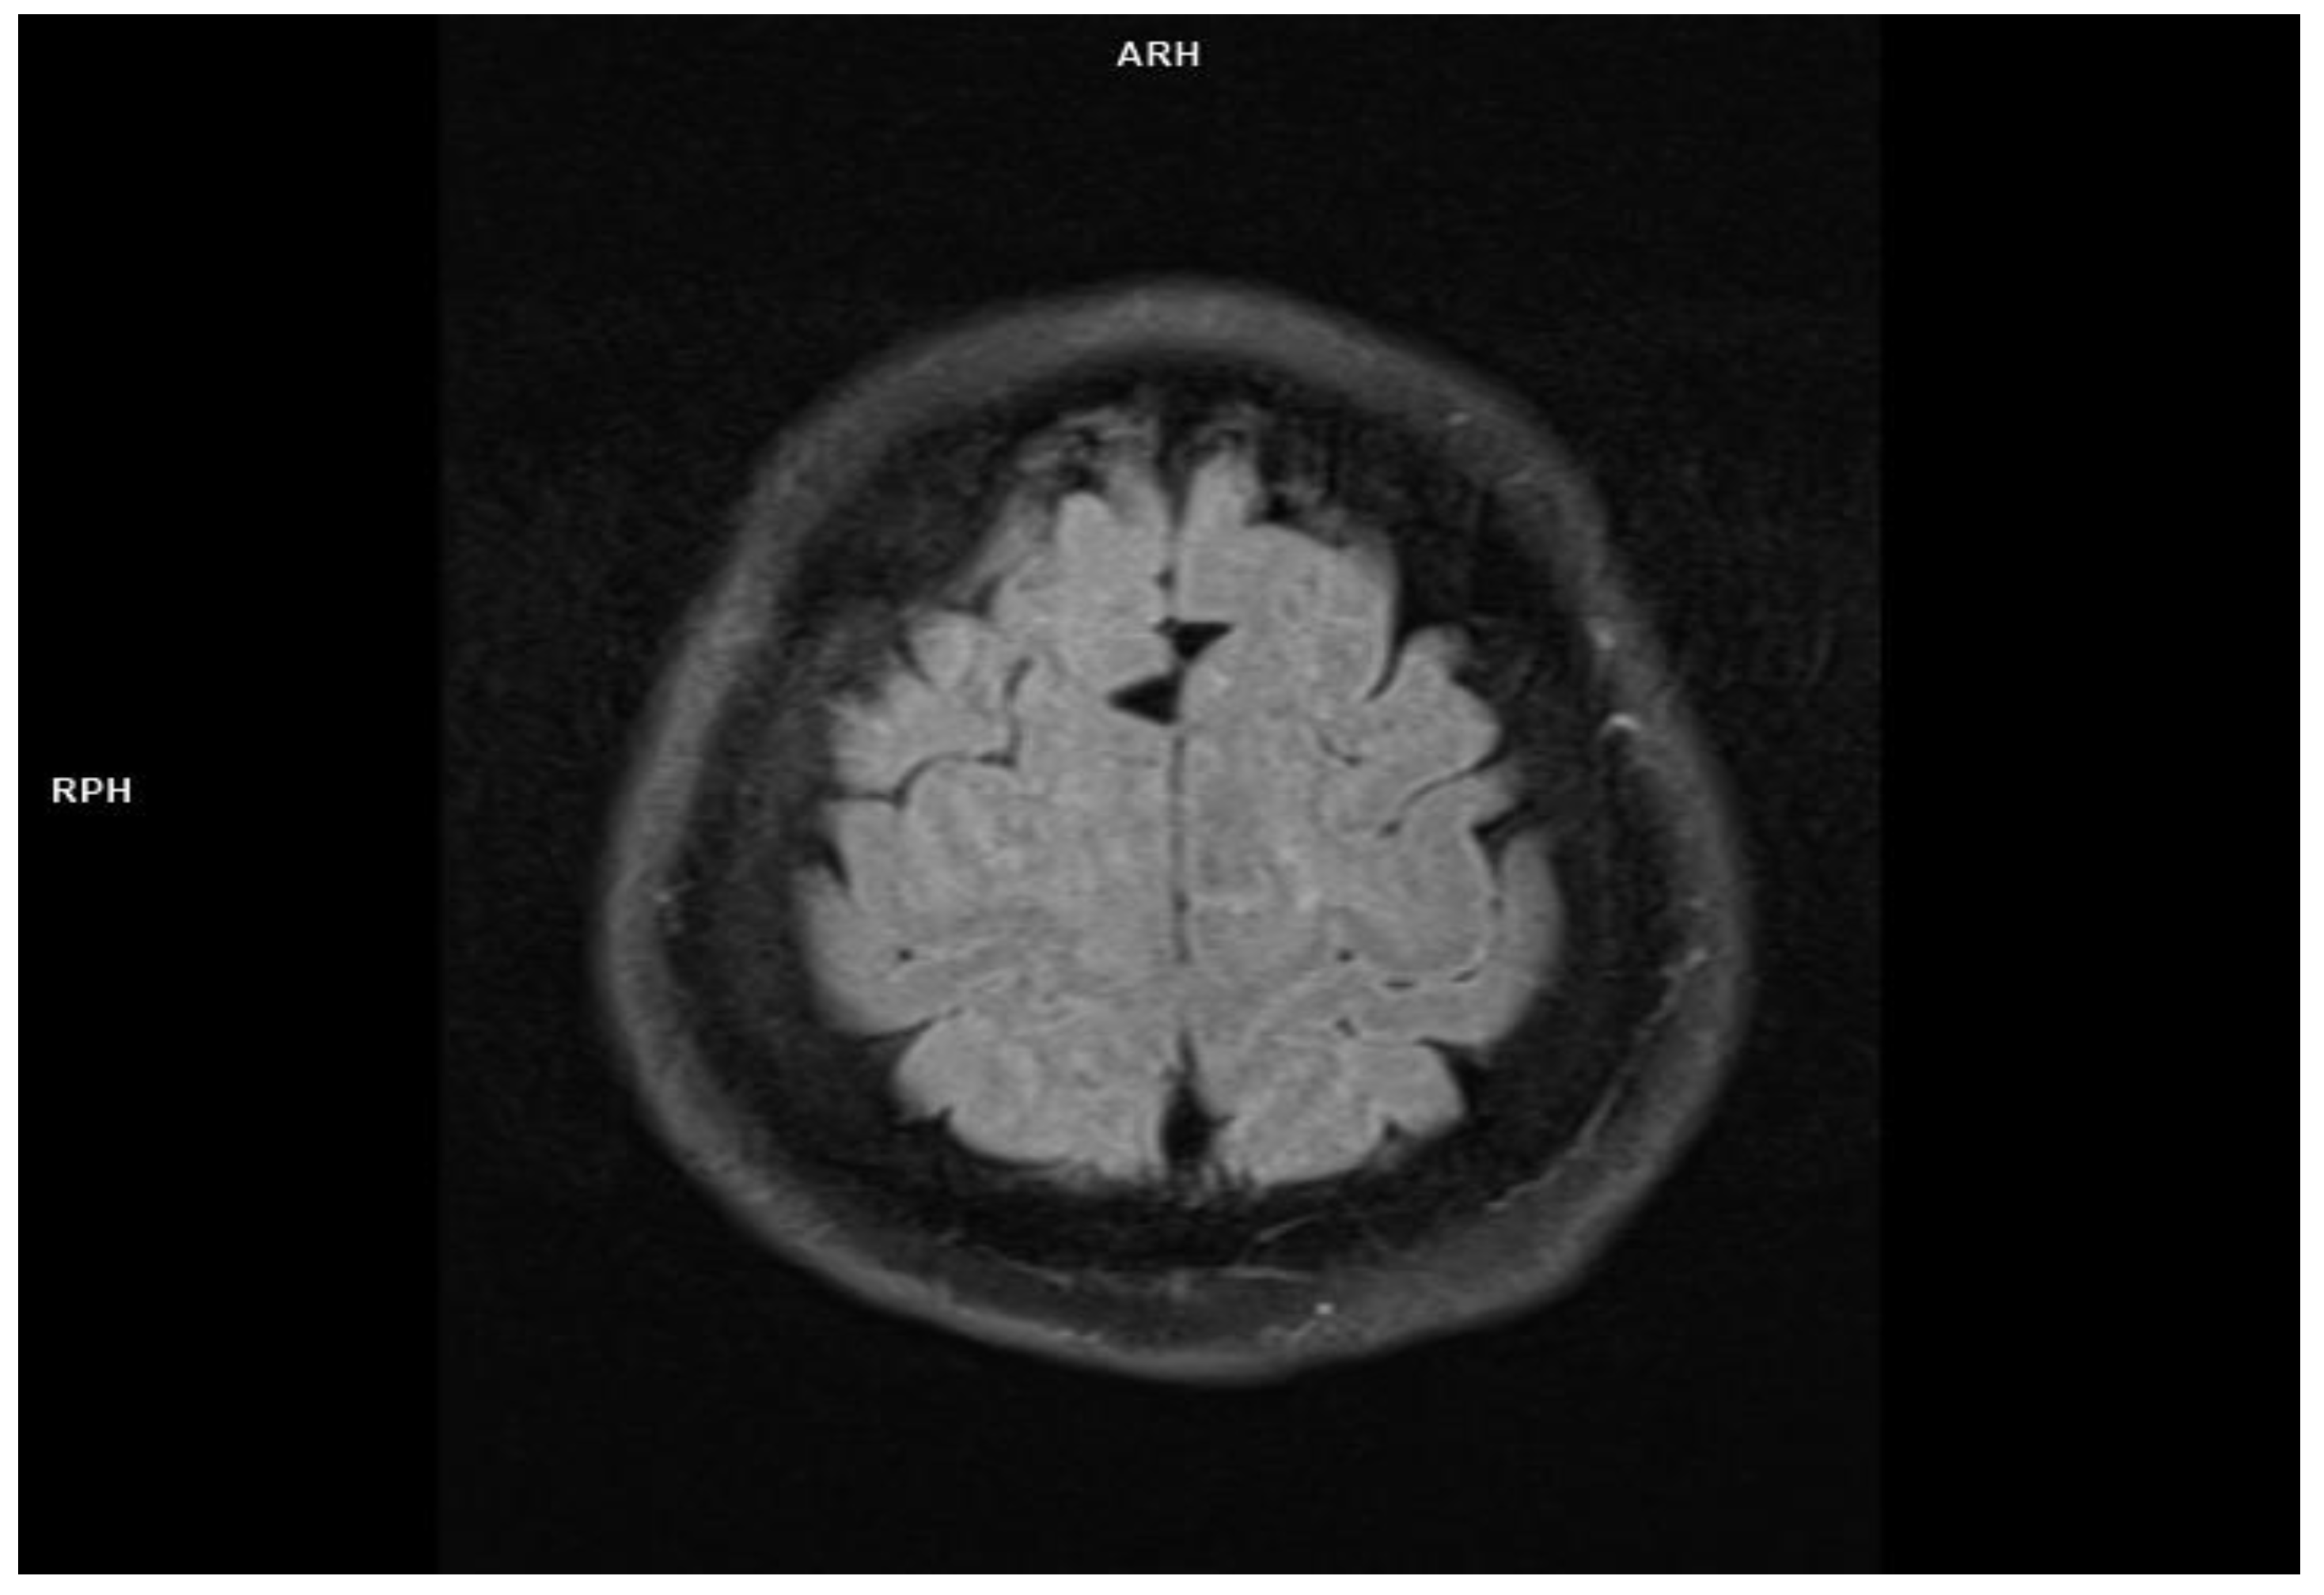

2.1. Patient 1